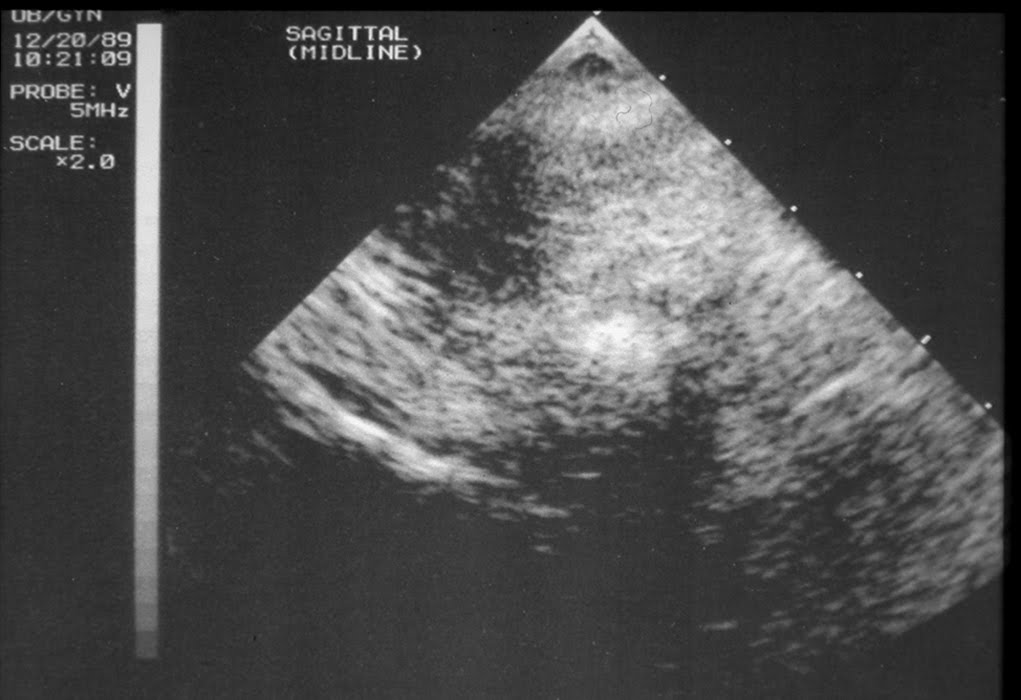

This is a midline (sagittal) view. The uterus is visible, but no endometrium is seen, because we are in the plane of the uterine septum. A cursor in the lower right of the photo marks the top of the uterus.